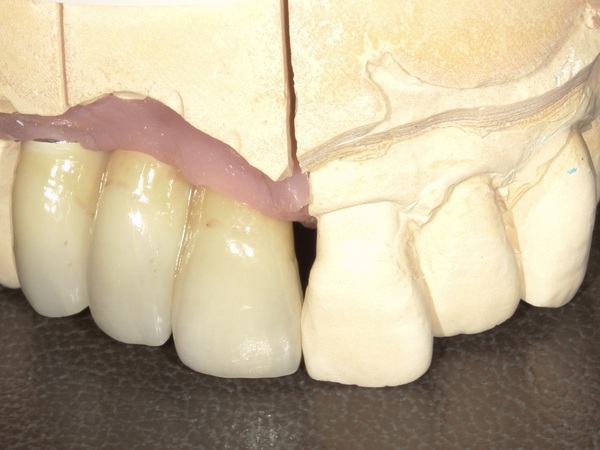

こちらが前歯のジルコニアセラミックの写真になります。よく見るとジルコニアにセラミックが足されているのが分かります。

技工士さんが写真を見ながら、歯の根の色や細かい色調を似せて作っていきますので、自然の歯にかなり近い状態で被せ物が再現されております。